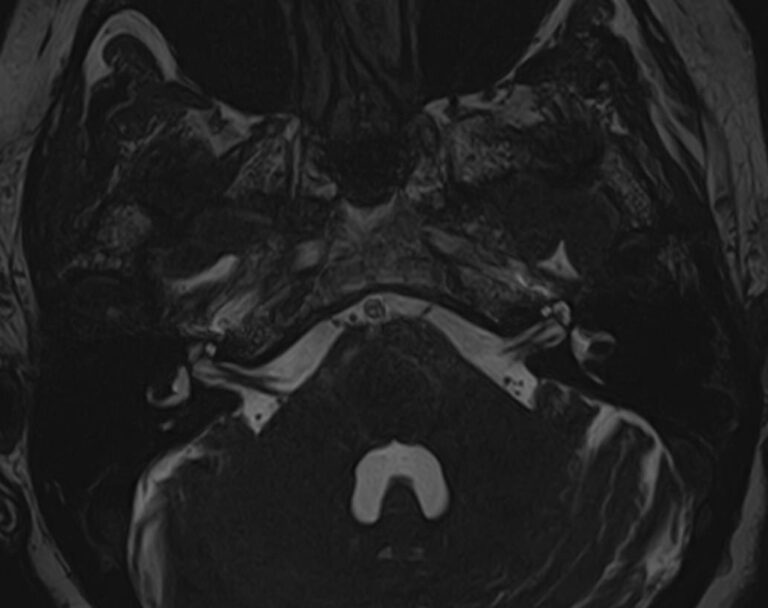

Мосто-мозжечковый угол — это пространство вблизи основания черепа в виде углубления между анатомическими образованиями: продолговатым мозгом, мозжечком и Варолиевым мостом. В этой области располагаются волокна многих черепно-мозговых нервов (например, лицевого, тройничного, преддверно-улиткового), проходят мозговые артерии и многочисленные вены мозжечка.

В мосто-мозжечковом угле часто развиваются воспалительные процессы (арахноидиты) с формированием в дальнейшем арахноидальных кист. Могут выявляться аневризмы расположенных здесь артерий. Но чаще всего в этой области образуются объемные образования, как злокачественные, так и доброкачественные, которые сдавливают расположенные там нервные волокна, кровеносные сосуды и пути ликворного оттока. Наиболее часто встречающаяся опухоль этой области — невринома преддверно-улиткового нерва. В большинстве случаев она имеет доброкачественный характер, развивается, как правило, у людей трудоспособного возраста, преимущественно у женщин. Реже встречаются менингиомы и холестеатомы мосто-мозжечкового угла.

Самым информативным, при этом быстрым и безопасным, методом диагностики опухолей мосто-мозжечкового угла на сегодняшний день является магнитно-резонансная томография с контрастированием. В клинике «Доступная медицина» проводится эффективная диагностика патологии мосто-мозжечкового угла с использованием новейшего томографа TOSHIBA VANTAGE TITAN 1,5 Тесла. Высокая мощность магнитного поля 1,5 Тесла позволяет получить подробное изображение этой труднодоступной для диагностики области в различных плоскостях.

Контрастирование проводится контрастным веществом на основе солей гадолиния (химический элемент, относящийся к редкоземельным металлам). Применяемый контрастный препарат накапливается в патологическом очаге, за счет чего при сканировании усиливается его яркость изображения. Это дает возможность выявить опухоли малых размеров (до 3 мм) и назначить своевременное лечение. Кроме того, контраст заполняет просвет сосудов, благодаря чему на снимках появляется детальное изображение сосудистой сети. Это позволяет диагностировать патологическую извитость, аневризмы, мальформации, при вазоневральном конфликте — зоны сдавления черепно-мозгового нерва кровеносным сосудом.